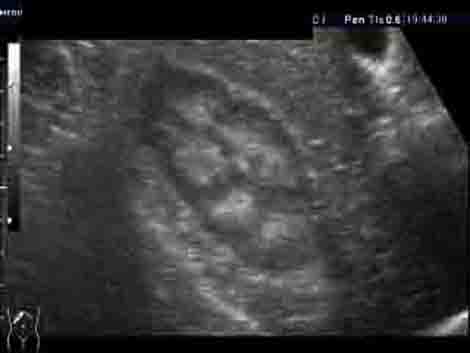

Женщина 50 лет. Прооперирована месяц назад по поводу альдостеромы левого надпочечника. Плановое УЗИ почек и надпочечников после операции. У нас смотрится впервые.

На УЗИ выявляю изменения в почках - см. фото. Паратгормон и уровень мочевой кислоты в норме. Креатинин 100-110. Меня старательно уверяют, что почки нормальные. И на МРТ, сделанной перед операцией, почки были якобы не изменены (но снимки потеряли). Отправил пациентку за копией снимков (в "живом" или цифровом варианте). Но большой надежды на восстановление данных нет.

Как вам кажется, коллеги: это нормальные почки? Я не исключаю в т.ч. и один из вариантов "губчатой почки".

Правая почка.

Левая почка.

Сонографическая картина нефрокальциноза. В некоторых пособиях такую картину называют "почками Андерссон-Карра".